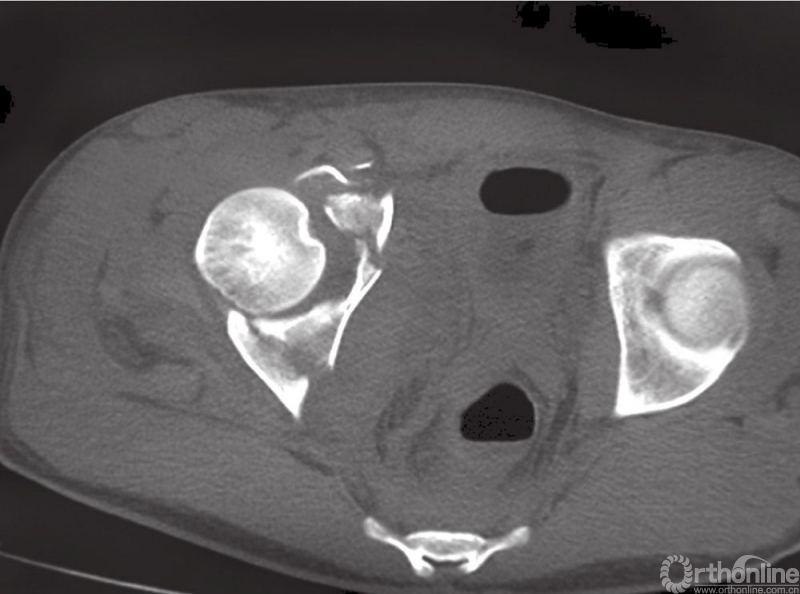

沿骨盆边缘预弯钢板

使用非对称骨盆复位钳复位四边体

复位的步骤是:首先,复位前柱粉碎骨折块的高出部分,它们本来位于后方;使用Shanz针控制髂嵴,使用内旋力使前柱内旋,使其靠近后柱,并通过中间窗触诊骨折复位情况;稍微过度弯曲髂嵴和髂窝钢板,有助于维持内旋和复位。再使用长的预弯钢板复位和固定前柱骨折块。单独复位四边体,使用偏心的骨盆复位钳维持复位。

因此,在骨盆边缘的内侧,四边体的表面放置钢板是一种非常重要的技术。可以通过髂腹股沟入路或者Stoppa入路都可以完成上述操作。通过第一窗进行观察,可以在耻骨支和四边体表面之间放置钢板。将骨盆重建钢板预弯放置在四边体的表面,从内向外置入螺钉,支撑四边体。